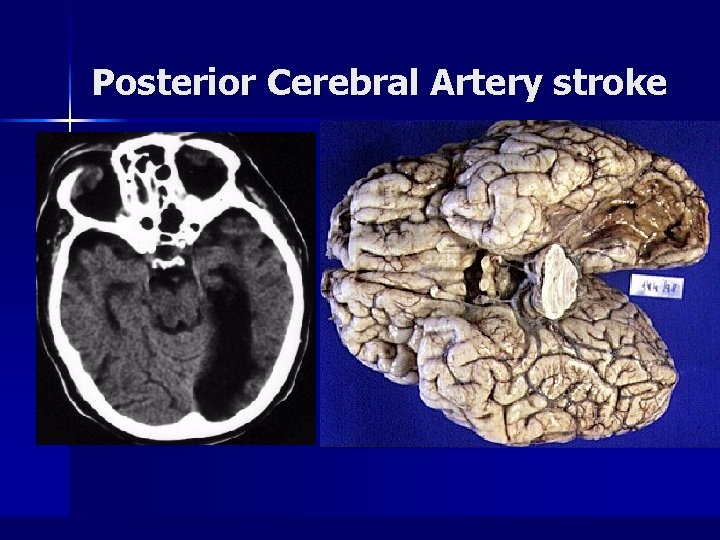

Posterior Cerebral Artery stroke